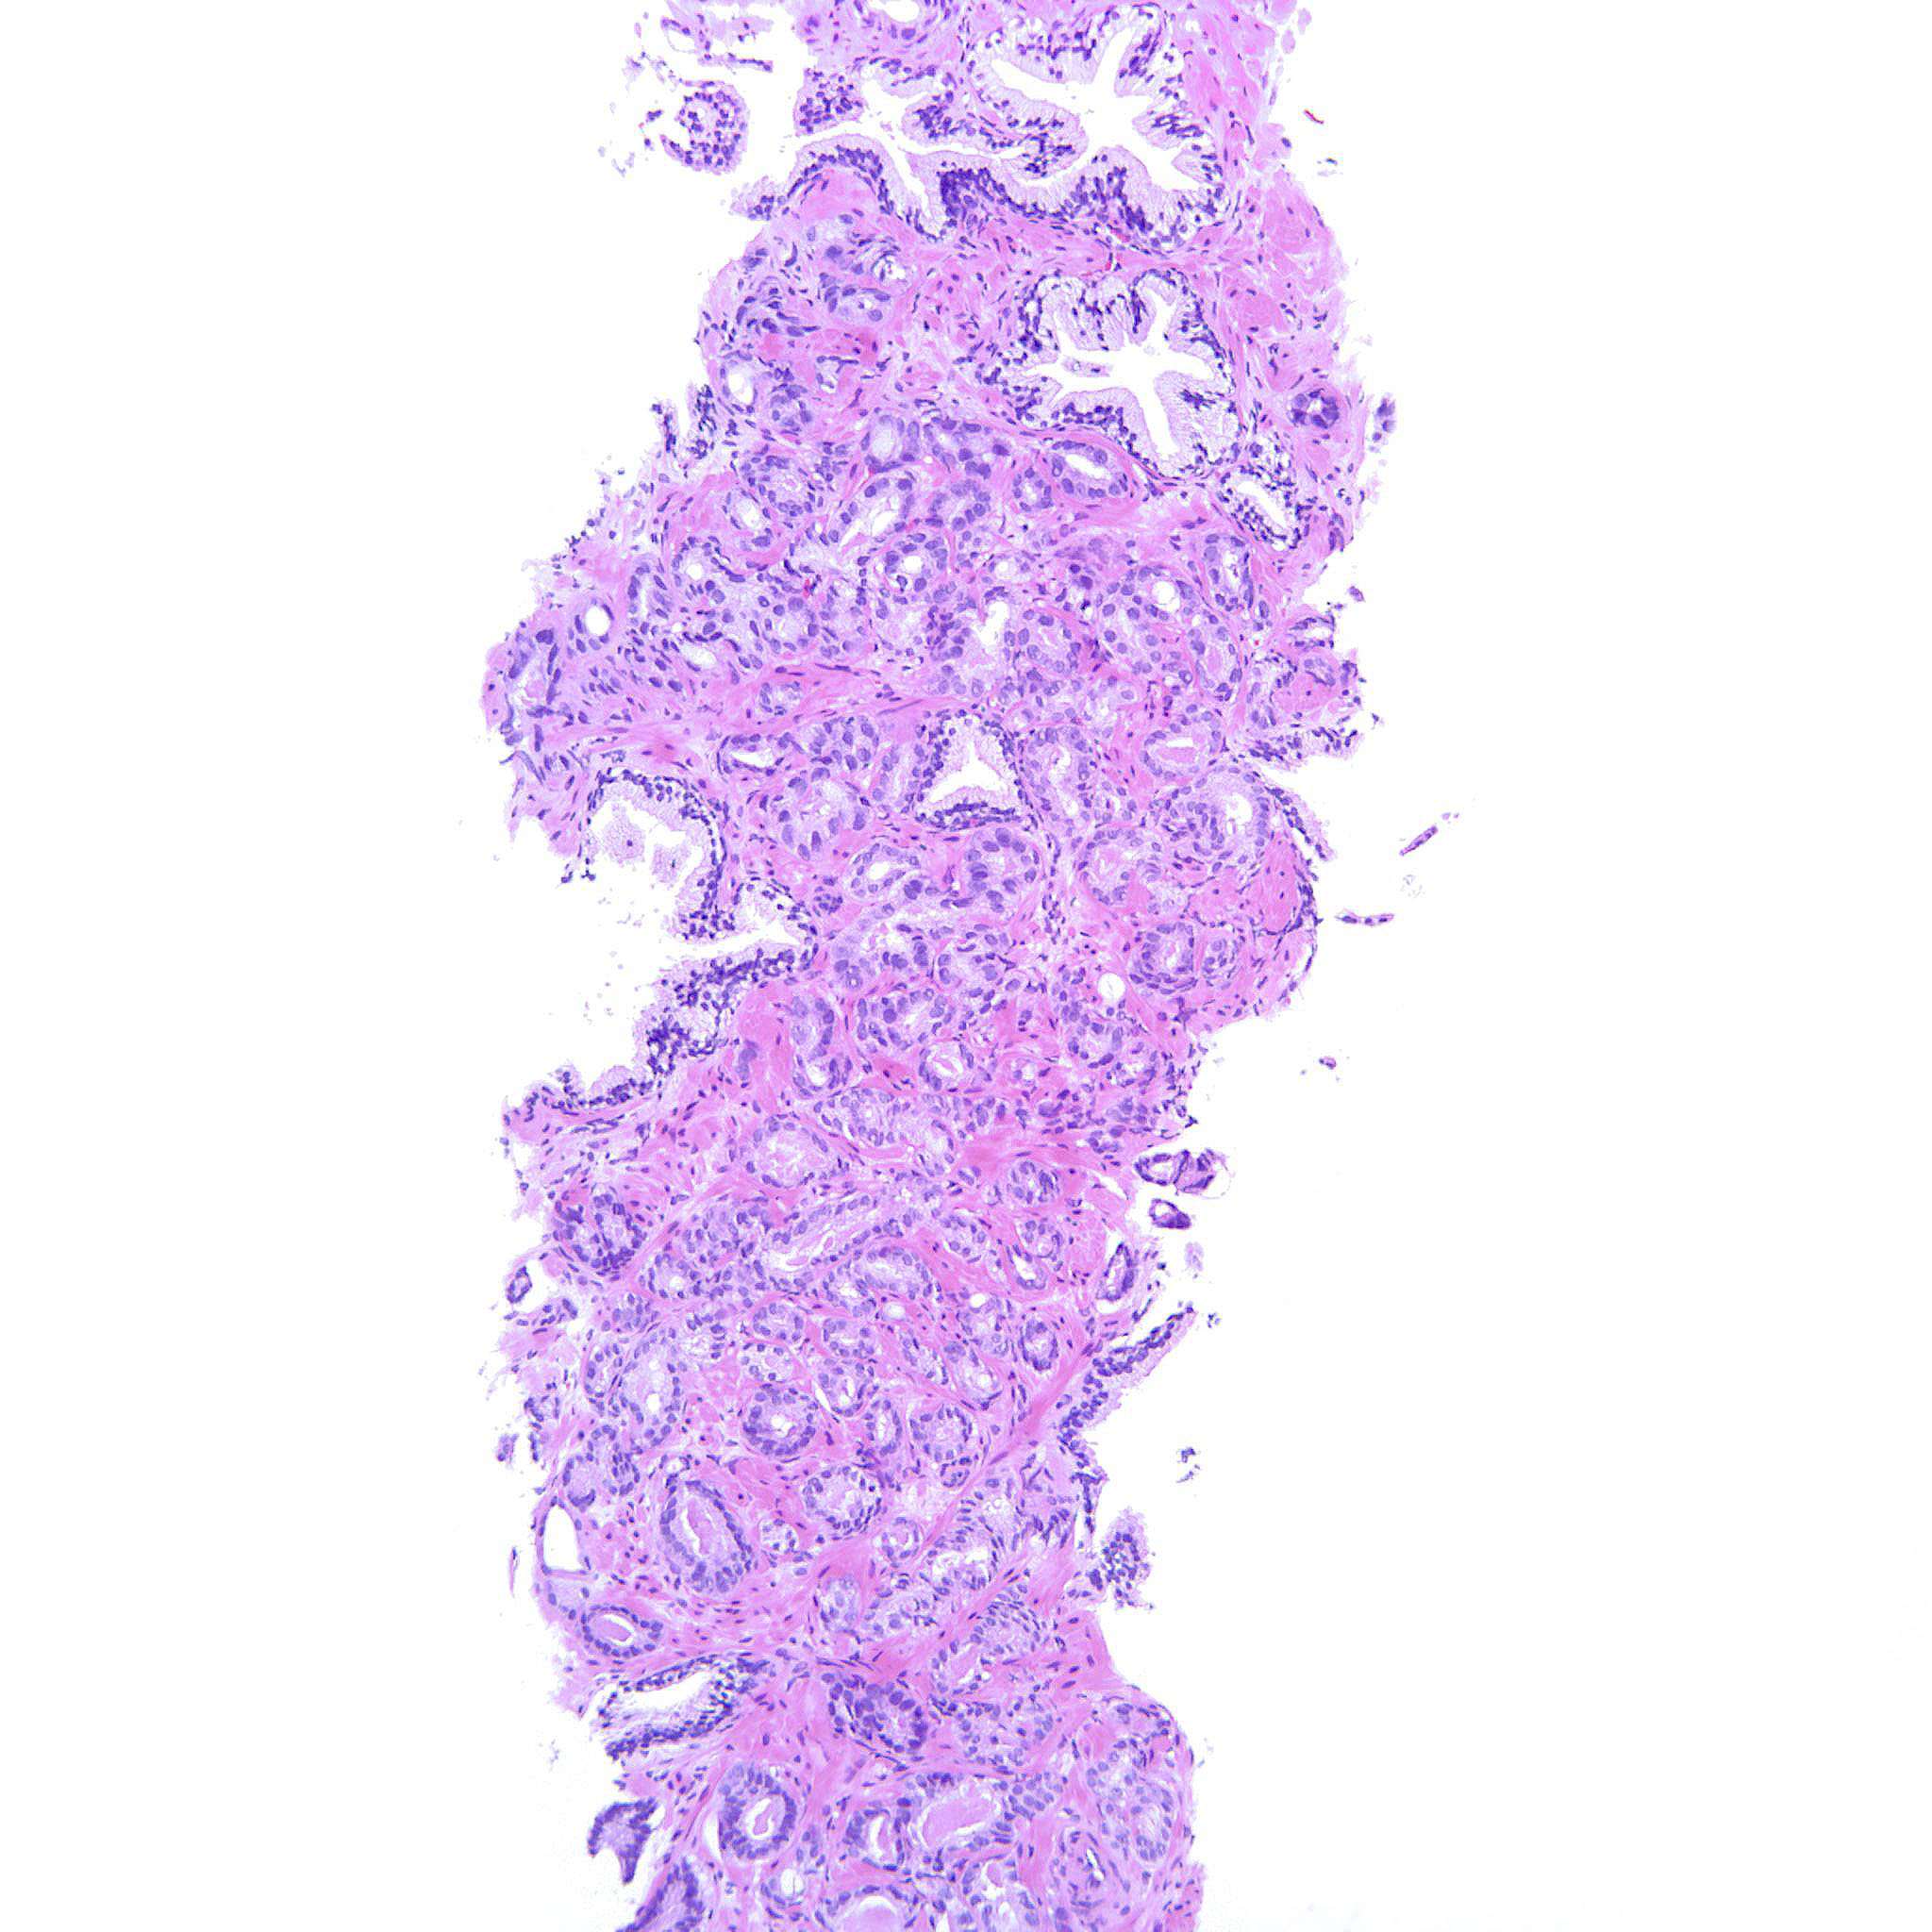

Prostate cancer grading

Case ID: 207